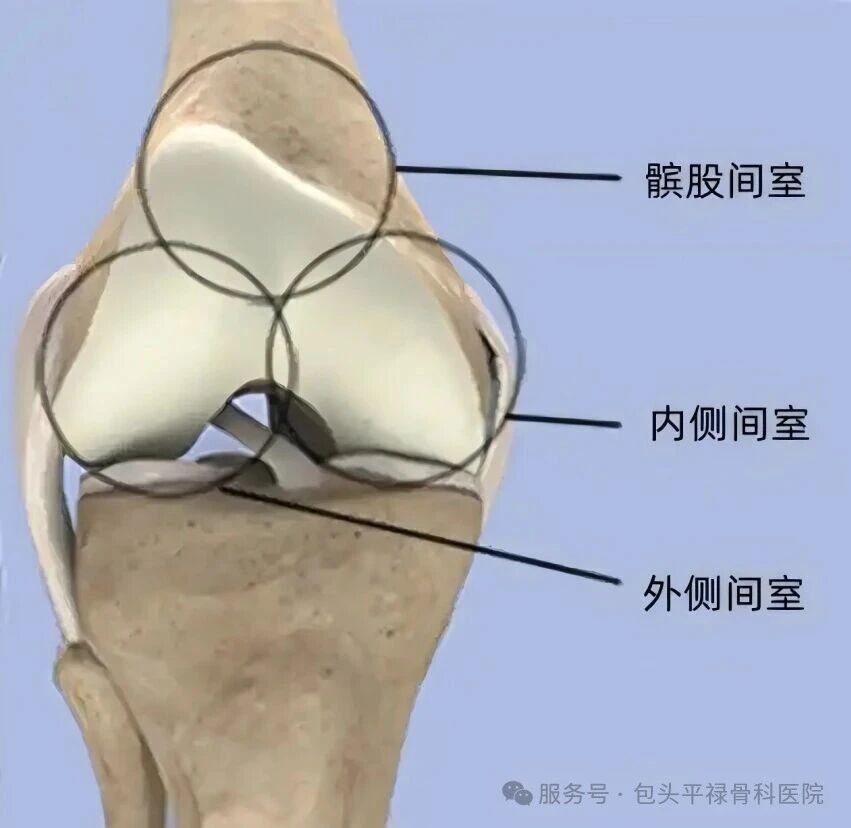

我们可以把膝关节想象成有三个“房间”的套房:

内侧间室(膝盖内侧)

外侧间室(膝盖外侧)

髌股间室(膝盖骨与股骨之间)

大多数的早期至中期膝关节炎,并不是所有“房间”都坏了,往往只是其中一个“房间”磨损严重(内侧间室最常见),而其他两个房间及关节的主要韧带仍然是健康的。